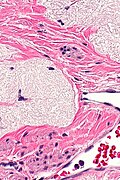

Ablated_endometrium. H&E stain. | |

| LM | endometrium completely or partially replaced by hyaline material and fibrosis |

Microscopic

Features:

- Endometrium completely or partially replaced by:

- Hyaline material, fibrosis.